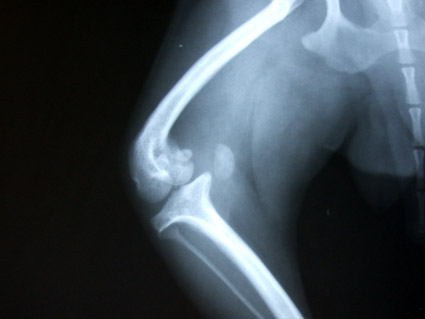

變形的左後腿,兩隻腳骨已呈現90度扭轉變形,韌帶也完全萎縮.

醫生說,如果要賭賭看,這條腿也可以開刀試試.

但不保證可以恢復到什麼程度,或是,開刀是否有幫助.